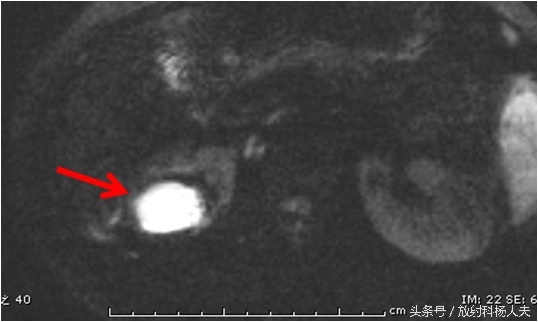

这个囊性病变到底是什么?囊性肿瘤?有无办法继续明确呢?有!那就是MRI,除了进一步明确,还能更清楚的显示窦道的走行。下图这个序列,叫DWI,红箭所示的白白的东西,证明这是一个脓肿!